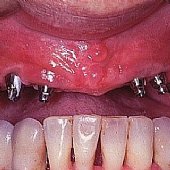

Bilder: Zahnimplantate bei Zahnlosigkeit im Unterkiefer

• Versorgung mit 5 Implantaten zur Aufnahme der festsitzenden Unterkieferbrücke.